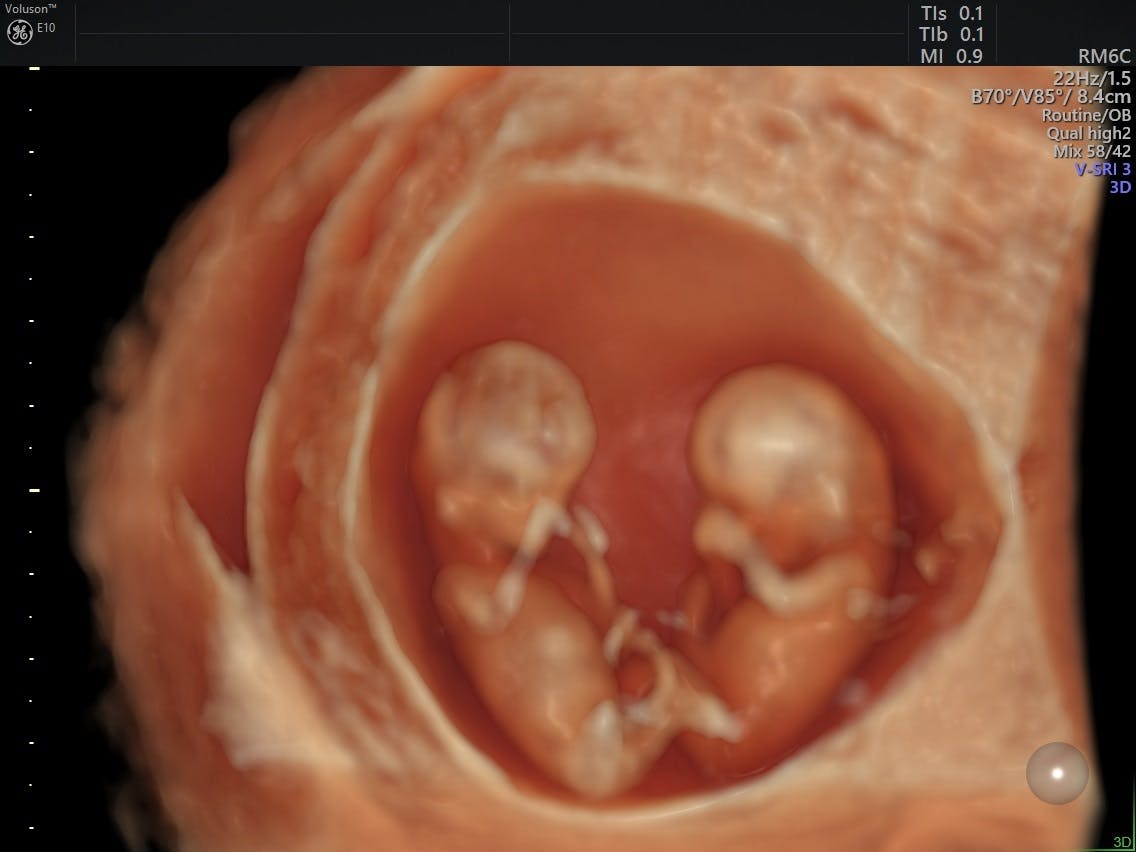

From www.volusonclub.net